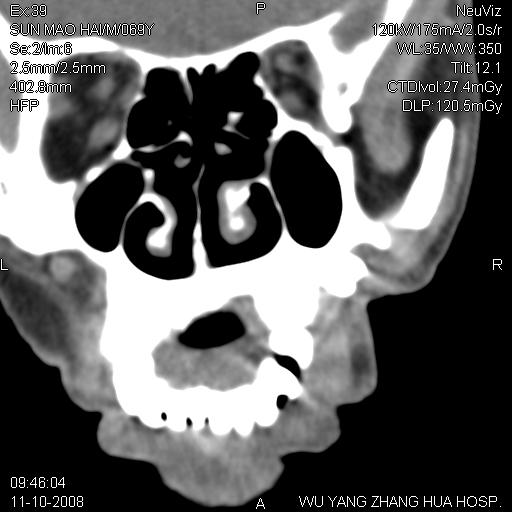

标题: CT16568:右面部瘘管半年余,无其它不适. [打印本页]

标题: CT16568:右面部瘘管半年余,无其它不适.

考虑右上颌异位齿(或斜向阻生齿)并根尖脓肿。

右上颌异位齿(或斜向阻生齿)

1.右上颌异位齿

2.右上颌化脓性骨髓炎

3.右下鼻甲肥大

支持三楼意见。(这种长法还真少见,再长再尖点就成獠牙了。)